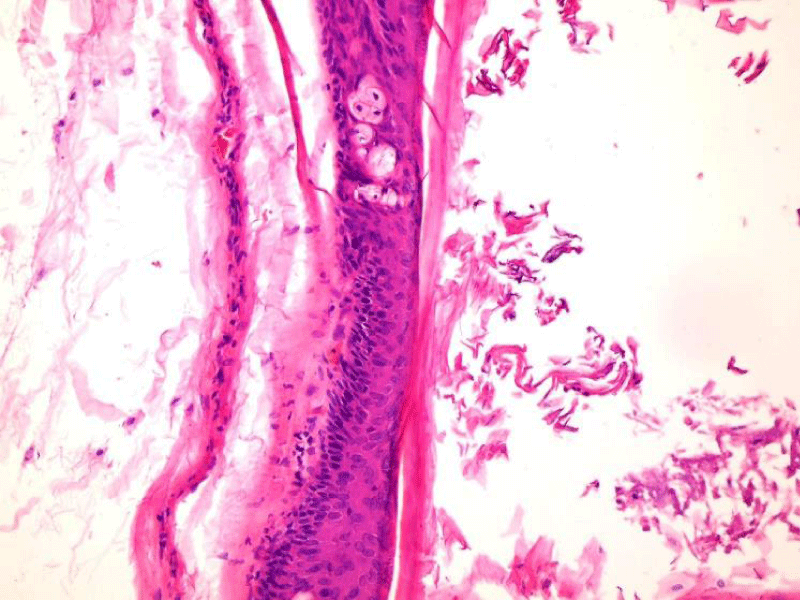

A 13-year-old female patient was admitted to our clinic with complaints of a gradually growing swelling in cervical region leading to difficulty to chew and swallow which was noticed approximately one year ago. A mass lesion measuring approximately 5x5 cm, filling mouth floor and could be observed on mid-cervical line on inspection, which is smooth, soft, mobile and which does not show heat increase was detected on physical examination (Figures 1,2). The mass lesion had a purplish protruded swelling mimicking plunning ranula in sub-mental region, it did not move with tongue movements. The patient had cosmetic concerns due to the lesion and it also had a disturbing appearance. Hemogram and biochemical analyses were normal. Ultra-sonography examination revealed a smooth, avascular, mobile, dense, cystic lesion measuring 6.5 x 4.5 cm. Tissue parts containing keratin and proteinous material were detected on FNAB examination. The patient and the family were informed about internal and external approaches and internal approach was recommended. Written informed consent was obtained from the patient and the family. A 3 cm of horizontal incision was done from 1.5 cm posterior of anterior incisors between Wharton ducts by preserving them under general anesthesia and the mass lesion was accessed after resection of soft tissues (Figures 3,4). The lesion was released over mylo-hyoid muscle and neighboring tissues by preserving its capsula and removed thereafter. It was seen not to adhere to hyoid bone and other tissues, consistently with its benign nature. Mouth floor was repaired with primary suturing. No post-operative complications occurred. The mass lesion was measured as 6.5 x 5 cm and weighed 50 gr. ((Figures 5,6). A cystic lesion covered with squamous epithelium and keratinized cystic structure was observed. Basophilic "dot like" staining was observed in acidophilic stratum corneum and stratum granulosum (Figure 7). No post-operative complications occurred and recurrence was not detected in 2-year follow up.

Differential diagnosis of cervical epidermoid cysts include thyro-glossal cyst, dermoid cyst, inclusion cyst, branchial cyst, sub-mandibular and sub-lingual gland infection, pleomorphic adenoma, cystic higroma, lympho-epthelial cyst, lipoma, neuro-fibroma, hemangioma and lymph-angioma [6]. Physical examination findings of our patient were consistent with plunging ranula. However it was detected to be a giant epidermoid cysts as the result of pre-operative FNAB, intra-operative findings and post-operative histological findings. "Stratum granulosum" is a specific histo-pathological finding for epidermoid cysts [11]. Basophilic "dot like "staining in acidophilic stratum corneum and stratum granulosa was prominent on histo-pathological examination of the lesion. Definite diagnosis of "epidermoid cyst" was made with abovementioned histo-pathological findings.